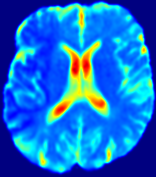

LesionRefer to captionRefer to captionRefer to captionRefer to captionRefer to captionRefer to caption𝐕rgbsubscript𝐕𝑟𝑔𝑏{\bf{V}}_{rgb}Refer to captionRefer to captionRefer to captionRefer to captionRefer to captionRefer to caption𝐕2subscriptnorm𝐕2{\|\bf{V}}\|_{2}Refer to captionRefer to captionRefer to captionRefer to captionRefer to captionRefer to captionRefer to caption3.53.53.52.82.82.82.12.12.11.41.41.40.70.70.70.00.00.0(mm/s)𝑚𝑚𝑠(mm/s)D𝐷DRefer to captionRefer to captionRefer to captionRefer to captionRefer to captionRefer to captionRefer to caption0.0200.0200.0200.0160.0160.0160.0120.0120.0120.0080.0080.0080.0040.0040.0040.0000.0000.000(mm2/s)𝑚superscript𝑚2𝑠(mm^{2}/s)Slice #1Slice #2Slice #3Slice #4Slice #5Slice #6

Figure 4: PIANO feature maps for another patient in the ISLES 2017 training set, where the lesion is located in the right hemisphere. Top row: segmented stroke lesion region (white) on different slices. The corresponding slices for the PIANO feature maps are shown in the following rows.

For a better insight into an estimated velocity field 𝐕𝐕{\bf{V}} and diffusion field 𝐃𝐃{\bf{D}}, we compute the following maps: (1) 𝐕rgbsubscript𝐕𝑟𝑔𝑏{\bf{V}}_{rgb}: Color-coded orientation map of 𝐕=(Vx,Vy,Vz)T𝐕superscriptsuperscript𝑉𝑥superscript𝑉𝑦superscript𝑉𝑧𝑇{\bf{V}}=(V^{x},V^{y},V^{z})^{T}, obtained by normalizing 𝐕𝐕{\bf{V}} to unit length and mapping its 3 components to red, green, blue respectively; (2) 𝐕2subscriptnorm𝐕2\|{\bf{V}}\|_{2}: 222 norm of 𝐕𝐕{\bf{V}}; (3) D𝐷D: scalar field in Eq. 5.

Fig. 3 and Fig. 4 show the PIANO feature maps estimated from two ISLES 2017 patients: all are highly consistent with the lesion in both cases. Details of the blood flow trajectories are revealed in 𝐕rgbsubscript𝐕𝑟𝑔𝑏{\bf{V}}_{rgb} by the ridged patterns and the sharp changes of colors in the unaffected (right) hemisphere, while the flat patterns appearing within the lesion provide little directional information about the velocity and indicate low velocity magnitudes. Velocity magnitudes are more directly visualized via 𝐕2subscriptnorm𝐕2\|{\bf{V}}\|_{2}, from which one can easily locate the lesion where 𝐕2subscriptnorm𝐕2\|{\bf{V}}\|_{2} is low. D𝐷D also indicates lower diffusion values in the lesion, though with less contrast potentially due to the fact that it captures the accumulated effect of CA diffusion at the voxel-level.